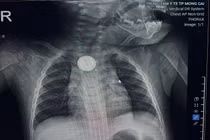

Kết quả X-quang cho thấy dị vật mắc lại ở thực quản. Các bác sĩ tiến hành nội soi cấp cứu và gắp thành công viên pin. Tuy nhiên, quan sát trực tiếp tại vị trí mắc cho thấy vùng thực quản đã bị ăn mòn và loét lớn - minh chứng pin cúc áo có thể gây tổn thương nặng nề chỉ trong thời gian rất ngắn, dù trẻ được đưa đến viện sớm.

Hình ảnh viên pin cúc trong thực quản bệnh nhi. Ảnh: Bệnh viện Nhi Hải Phòng

Hình ảnh dị vật là pin cúc áo trong thực quản trẻ. Ảnh: Bệnh viện Nhi Hải Phòng